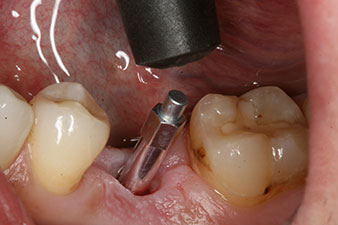

En outre, après avoir vissé une tige de mesure (SmartPeg) spécialement conçue pour l'implant, la valeur ISQ a été mesurée à l’aide de la sonde du module W&H Osstell ISQ.

Ce module est fourni en option avec l’Implantmed de W&H et est fixé au moteur d’implantologie (cf. Fig. 11). La valeur ISQ adimensionnelle mesurée immédiatement après l’insertion était de 64 dans l’axe oro-vestibulaire et de 68 dans l’axe mésio-distal (valeur maximale = 100).

Après cicatrisation des tissus mous, la stabilité de l’implant a été mesurée une nouvelle fois avant la pose de la restauration prothétique.

Les deux valeurs étaient pratiquement inchangées, situées entre la plage moyenne et la plage haute - la valeur la plus basse étant toujours utilisée comme valeur de référence qui détermine le traitement.

Par conséquent, il a été possible d’enregistrer une ostéo-intégration réussie et une stabilité biologique correcte, permettant également de prendre une empreinte durant la même séance.